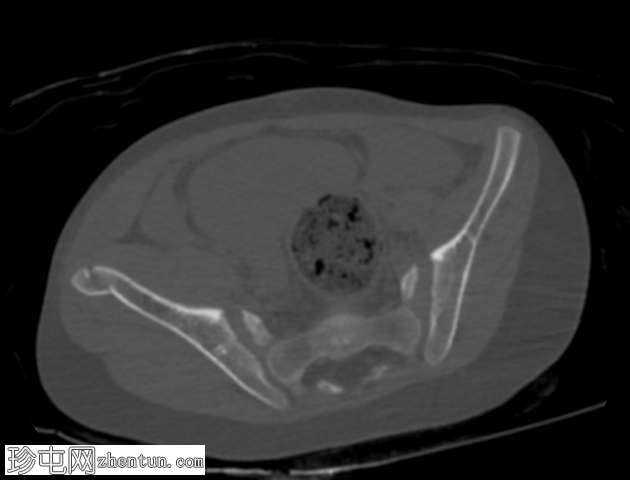

轴向骨窗

右髂前骨骨折。